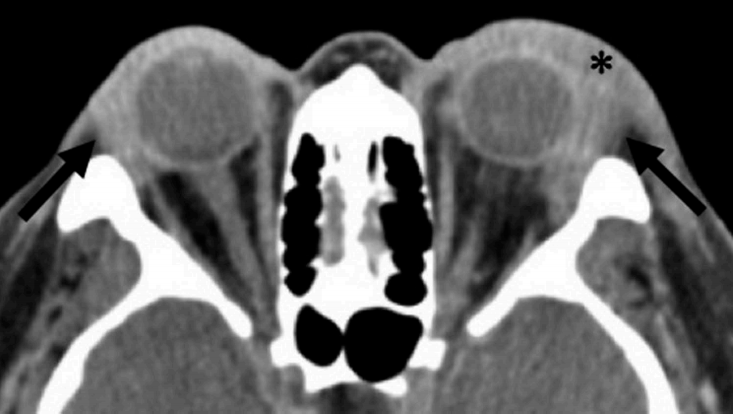

病例透视 | 易被误诊的眼眶炎性假瘤

病史摘要:42 岁男性患者,主因“左眼疼痛、肿胀 2 周”就诊。既往有五年高血压病史,控制良好,否认发热、寒战等其他异常症状。初诊被诊断为左眼睑板腺炎,予抗菌药物治疗。诊疗过程:初诊眼科检查,右眼视力 1.0,左眼 0.5,左眼眼睑红肿等。1 周后症状加重伴视力模糊复查,眼眶 MRI 增强扫描显示眼眶软组织弥漫性增强等异常。经疑难病例讨论,怀疑 TAO 或眼眶炎性假瘤,实验室检查后